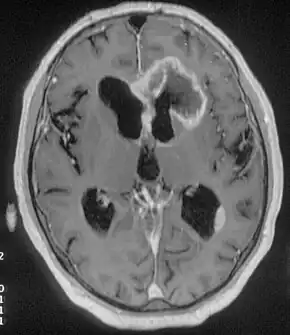

Neuroimaging

Advancements in technology, has given rise to newer, more efficient methods of diagnosis, most prominent being in the domain of neuroimaging.[18] The high spatial resolution from fMRI has implications on certain brain regions contributing to memory.[18] The usage of task fMRI for examination of memory or other higher cognitive networks may also be used to predict ictal onset zone(s) in patients with FLE, giving the advantage of refinement of patient-specific analyses.[18] The use of multi-modal approaches in association with neuroimaging techniques like fMRI and MEG or EEG will be informative in characterizing atypical functional brain networks in FLE.[18] But, difficulty remains in the evaluation of potential compensatory mechanisms between patients with FLE with normal and impaired memory, without properly characterizing transfer of information during memory tasks.[18]

Positron emission tomography (PET) helps to locate epileptogenic loci.[9] If the MRI were normal the PET scan could locate some abnormalities.[9]